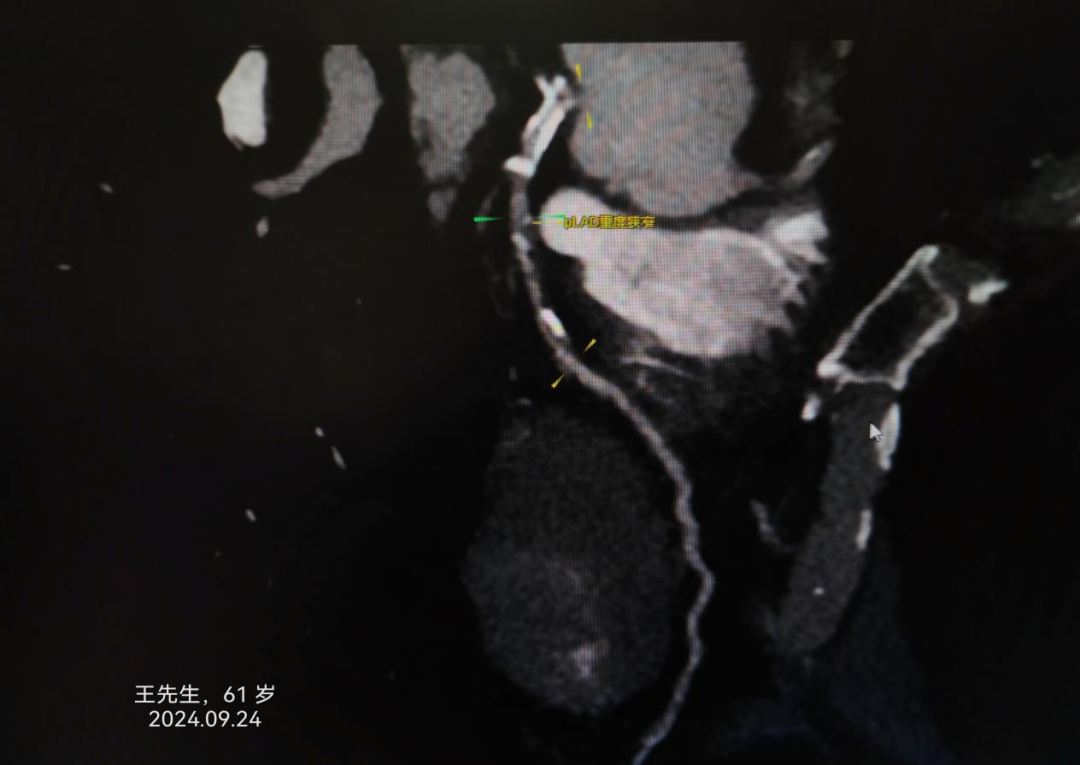

冠心病患者是猝死的高危人群。冠心病是中老年人最常见而且危害最大的心脏病之一,但随着生活节奏的加快和压力的增加,年轻人发病率也呈现增高的趋势。患者轻者可能无明显症状,但严重者可能会因此丧命。及时了解冠心病的早期症状对于早期发现和早期治疗有很大的帮助。